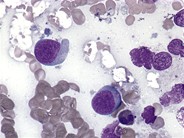

T Cell Lymphoma - Subcutaneous panniculitis-like T-cell lymphoma. a An ... - Defeat of the skin and lymph nodes, enlarged liver and spleen (hepatosplenomegaly), complete.

hepatosplenic T cell lymphoma 1

hepatosplenic T cell lymphoma 1 from imagebank.hematology.org